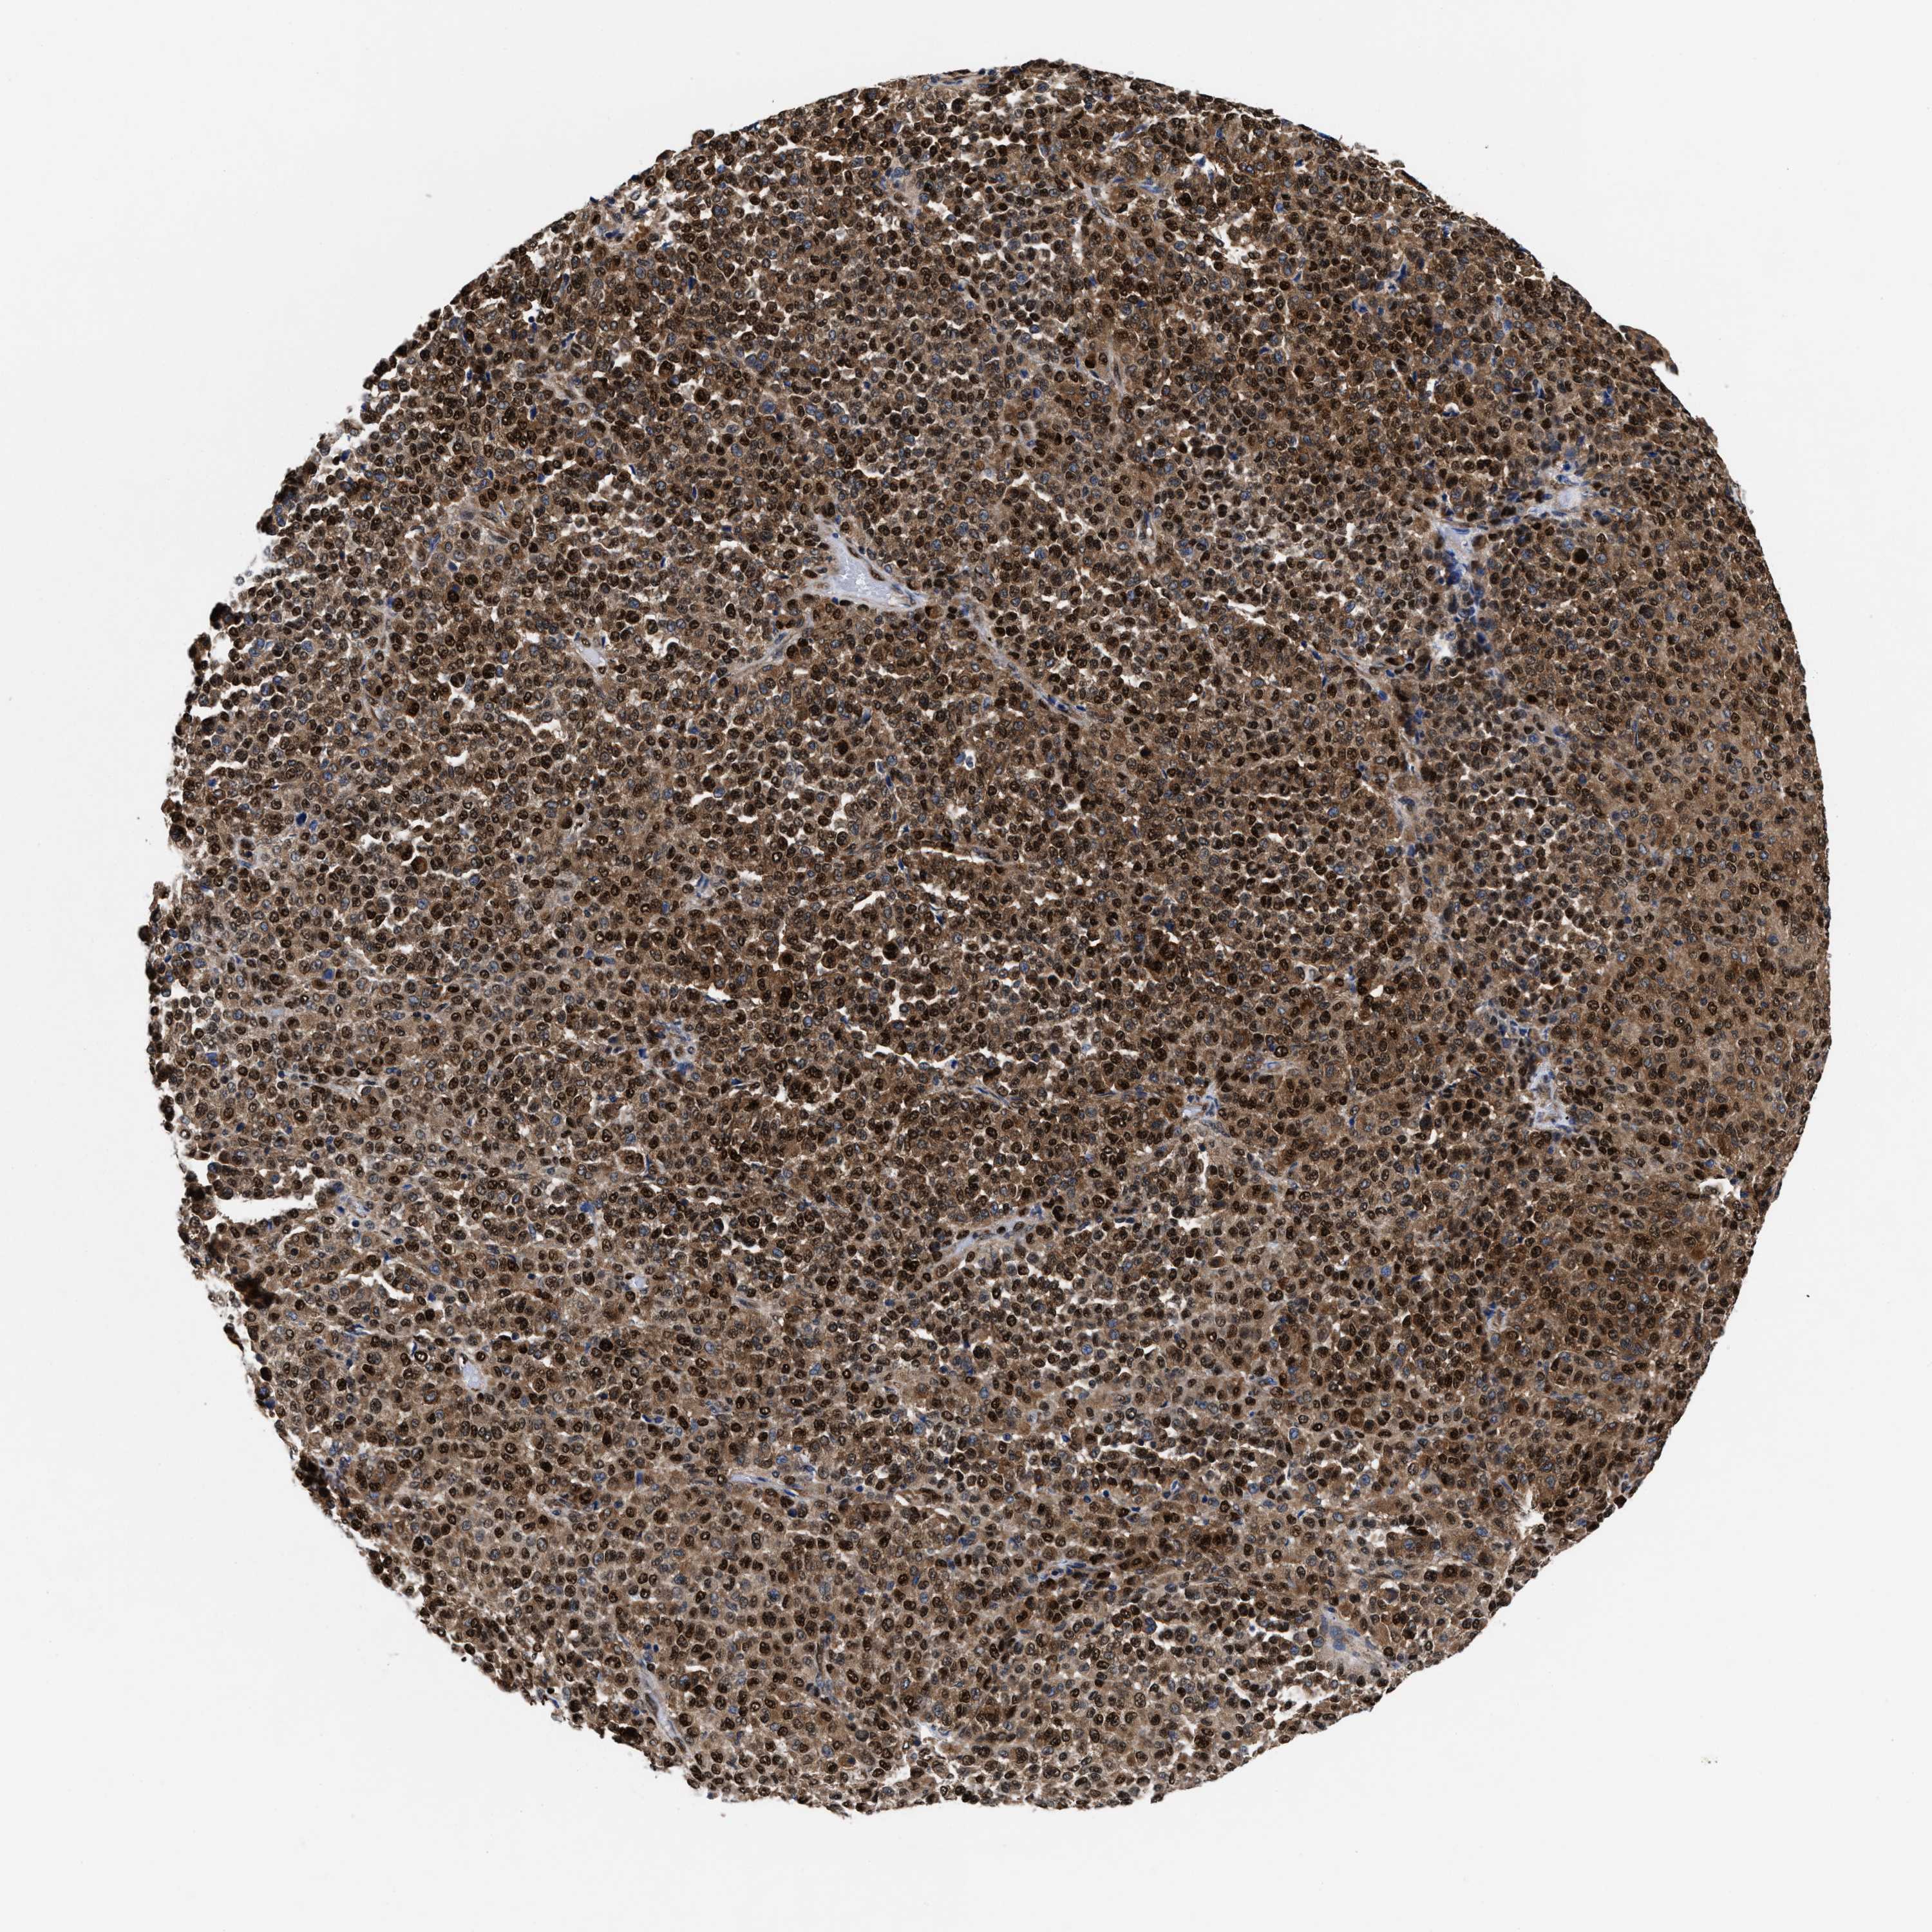

MELANOMA - Protein expressioni

A mouse-over function shows sample information and annotation data. Click on an image to view it in a full screen mode. Samples can be filtered based on level of antibody staining by selecting one or several of the following categories: high, medium, low and not detected. The assay and annotation is described here.

Note that samples used for immunohistochemistry by the Human Protein Atlas do not correspond to samples in the TCGA dataset.

Antibody stainingi

Antibody staining in the annotated cell types in the current human tissue is reported as not detected, low, medium, or high, based on conventional immunohistochemistry profiling in selected tissues. This score is based on the combination of the staining intensity and fraction of stained cells.

Each image is clickable and will lead to virtual microscopy that enables deeper exploration of all samples and also displays staining intensity scores, fraction scores and subcellular localization as well as patient and tissue information for each sample.

HPA022434

HPA022953

HPA022959

HPA028758

CAB007783

Staining

High

Medium

Low

Not detected

Intensity

Strong

Moderate

Weak

Negative

Quantity

>75%

75%-25%

<25%

None

Location

Nuclear

Cytoplasmic/membranous

Cytoplasmic/membranous,nuclear

Malignant melanoma, NOS

Malignant melanoma, Metastatic site